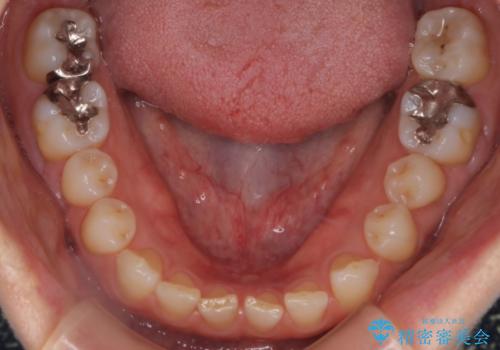

- 前歯のすきっ歯が気になるということで来院されました。今回は抜歯はしないためワイヤー矯正かインビザライン矯正のどちらでも治療可能でしたが、患者さまのご希望により表のワイヤー装置にて治療をおこないました。

前歯に隙間がいくつかあったため、今回は上下でゴムかけを行いスペースを埋めるための力をかけて閉じました。もう少し早く終了する予定でしたが、ブラッシング不良による歯肉腫脹があり、一部スペースクローズに時間がかかりました。